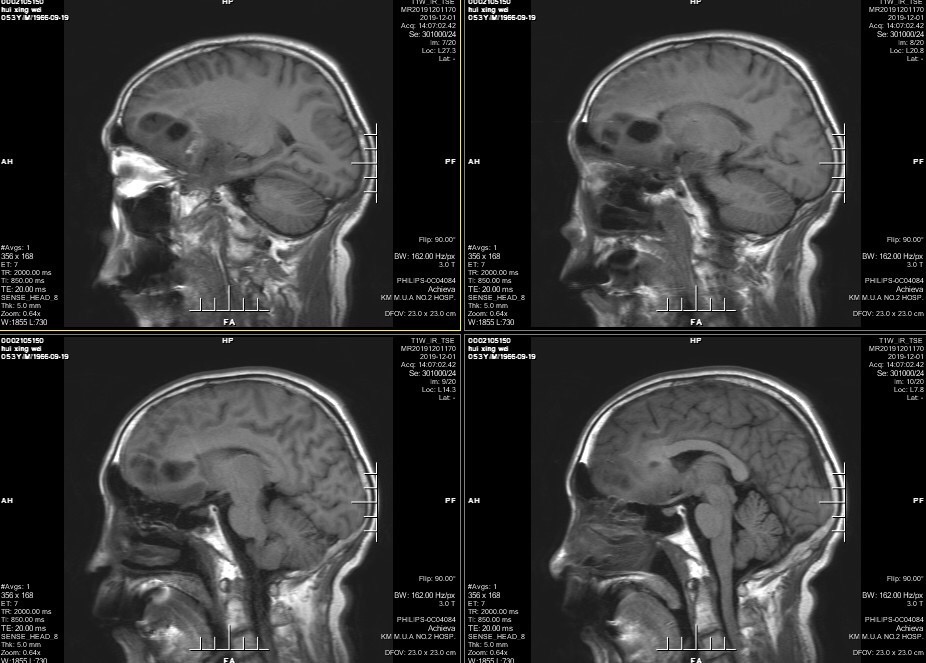

男性患者,53岁,主诉:反复头痛伴恶心一周,突发意识丧失一次。入院查体:神经体统无阳性体征。入院头颅MRI:左额叶胼胝体区囊实性占位,不均匀强化,考虑高级别胶质瘤;长程视频脑电监测提示左侧中央区、顶区、后颞区见中等量低-中-高波幅痫样放电。术前诊断:1.左额叶胼胝体区占位病变;2.继发性癫痫,入院给予降颅压及抗癫痫处理,积极完善术前准备后于2019年12月3日全麻下完成手术,术中行B超引导下切除肿瘤。术后患者无肢体功能及语言功能障碍,复查头颅核磁肿瘤全切,一周后出院开始放化疗治疗。

肿瘤为囊实性。

双侧大脑前动脉受肿瘤推挤。

增强后不均匀强化。